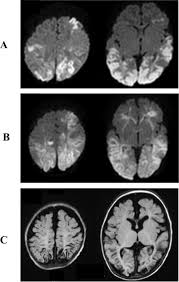

Herpes simplex (hsv) encephalitis is the most common cause of fatal sporadic fulminant necrotizing viral encephalitis and has characteristic imaging findings. Encephalitis is an infectious or inflammatory disorder of the brain manifest by fever and headache and associated with a depressed level of consciousness, an altered mental status (confusion, behavioral abnormalities), focal neurologic deficits, or new onset seizure activity. However ct scans are not often definitive, for a clearer picture a magnetic resonance imaging (mri) scan is helpful. The above described radiological findings are impressive of herpes simplex encephalitis. Mri is the preferred imaging modality for hsv encephalitis.

Herpes simplex (hsv) encephalitis is the most common cause of fatal sporadic fulminant necrotizing viral encephalitis and has characteristic imaging findings. In some cases, advanced imaging techniques such as computed tomography and magnetic resonance imaging (mri) can maertzdorf j, et al. Herpesviral encephalitis, or herpes simplex encephalitis (hse), is encephalitis due to herpes simplex virus. Mushroom sign of pyloric stenosis. The imaging findings of hsv encephalitis on ct may be initially normal or subtly abnormal. Brain ct scan must be urgently performed to rule out a brain lesion with mass effect that would contraindicate lumbar puncture. Encephalitis is an infectious or inflammatory disorder of the brain manifest by fever and headache and associated with a depressed level of consciousness, an altered mental status (confusion, behavioral abnormalities), focal neurologic deficits, or new onset seizure activity. Herpes simplex encephalitis (hse) is the most common cause of fatal sporadic encephalitis worldwide.

Rasmussen's encephalitis is a progressive hemispheric atrophy of unknown origin. Hsv1 encephalitis should always be considered on initial mri. Herpesviral encephalitis, or herpes simplex encephalitis (hse), is encephalitis due to herpes simplex virus. Multiple subtypes of the herpes virus family are neurotropic and may cause devastating neurologic injury. Herpes simplex (hsv) encephalitis is the most common cause of fatal sporadic fulminant necrotizing viral encephalitis and has characteristic imaging findings. The differential diagnoses include limbic encephalitis (paraneoplastic), gliomatosis cerebri, and status epilepticus. In some cases, advanced imaging techniques such as computed tomography and magnetic resonance imaging (mri) can maertzdorf j, et al. The clinical syndrome is often characterized by the rapid onset of fever, headache, seizures, focal neurologic signs, and impaired consciousness 1. The images show symmetrical bilateral putaminal vasogenic oedema with mild restriction on diffusion and no bleed. The mortality from hsv is high, so commencement of treatment with antiviral drugs (acyclovir) is recommended without delay with the typical radiological find. Herpes simplex encephalitis is a type of infectious encephalitis which happens when herpes simplex virus (hsv) enters the brain. Results in brain necrosis and liquefaction. Severe infection, particularly untreated herpes simplex virus (hsv) encephalitis, can cause brain hemorrhagic necrosis.

Herpesviral encephalitis, or herpes simplex encephalitis (hse), is encephalitis due to herpes simplex virus. The differential diagnoses include limbic encephalitis (paraneoplastic), gliomatosis cerebri, and status epilepticus. Typical mri features of herpes simplex encephalitis. Herpes simplex encephalitis is a type of infectious encephalitis which happens when herpes simplex virus (hsv) enters the brain. Contributed by mark cohen, m.d. But changes are not specific for hsv (e.g. The mortality from hsv is high, so commencement of treatment with antiviral drugs (acyclovir) is recommended without delay with the typical radiological find. Severe infection, particularly untreated herpes simplex virus (hsv) encephalitis, can cause brain hemorrhagic necrosis.

Herpes simplex encephalitis is a type of infectious encephalitis which happens when herpes simplex virus (hsv) enters the brain. The mortality from hsv is high, so commencement of treatment with antiviral drugs (acyclovir) is recommended without delay with the typical radiological find. Hsv encephalitis causes inflammation, hemorrhage and edema. Typical mri features of herpes simplex encephalitis. Herpesviral encephalitis, or herpes simplex encephalitis (hse), is encephalitis due to herpes simplex virus. Brain ct scan must be urgently performed to rule out a brain lesion with mass effect that would contraindicate lumbar puncture. In some cases, advanced imaging techniques such as computed tomography and magnetic resonance imaging (mri) can maertzdorf j, et al. Multiple subtypes of the herpes virus family are neurotropic and may cause devastating neurologic injury.